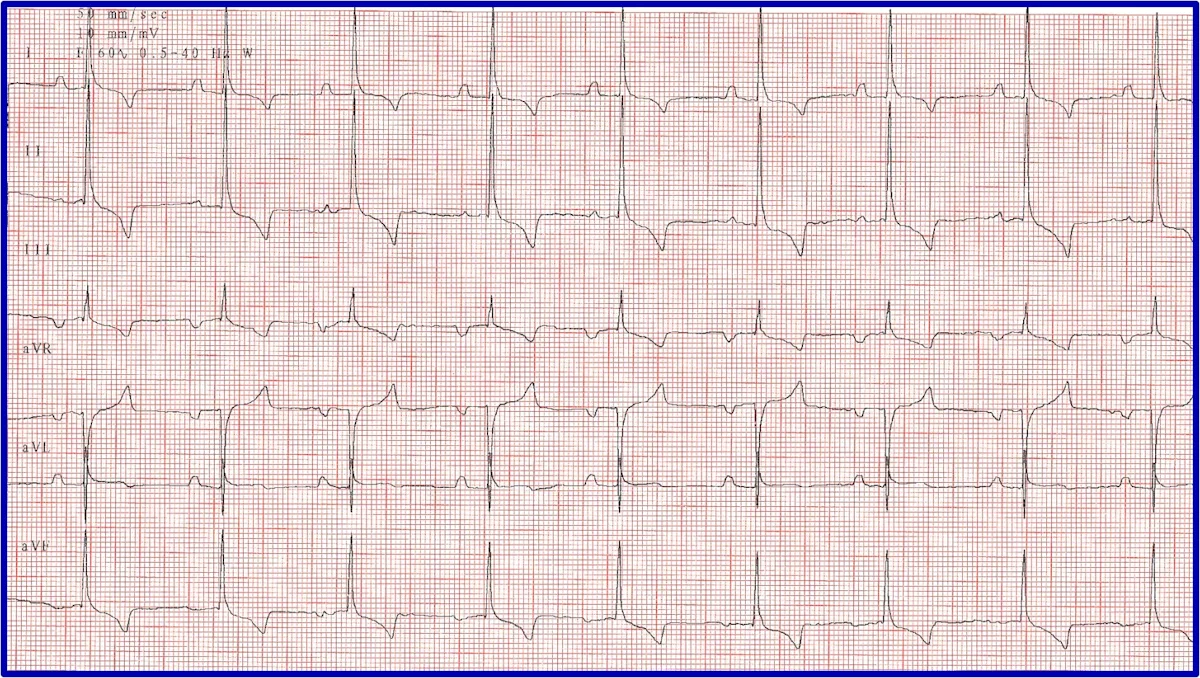

It is important to discern whether the arrhythmia is causing hemodynamic compromise by evaluating peripheral pulse quality, mucous membrane color, patient behavior, and arterial blood pressure. Sustained VT at a high rate is more likely to cause hemodynamic compromise than VT at a slower rate or AIVR (Figure 10). Determining whether the arrhythmia is likely to degenerate into ventricular fibrillation, which causes sudden death, is also important. Increased speed of VT or ventricular ectopic beats increase the likelihood that a beat will fall within the vulnerable period and induce ventricular fibrillation (ie, R on T phenomenon).

Two versions of ventricular runs of ectopy. (A) ECG showing a run of sustained true VT with a rate of 320 bpm in a boxer. (B) ECG showing an AIVR rhythm (ie, slow VT) in a crossbreed dog hit by a car and experiencing traumatic myocarditis. The rate is 180 bpm and not hemodynamically compromising the patient. A sinus beat occuring at the same time as a ventricular beat, causing a fusion beat (circle), can be seen.